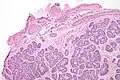

| Micrograph of a Sertoli cell nodule. H&E stain. | |

Sertoli cell nodules are unencapsulated nodules that consist of:[1][2][3]

- cells arranged in well-formed tubules (that vaguely resemble immature Sertoli cells), with

- bland hyperchromatic oval/round nuclei that are stratified, and

- may contain eosinophilic (hyaline) blob in lumen (centre).